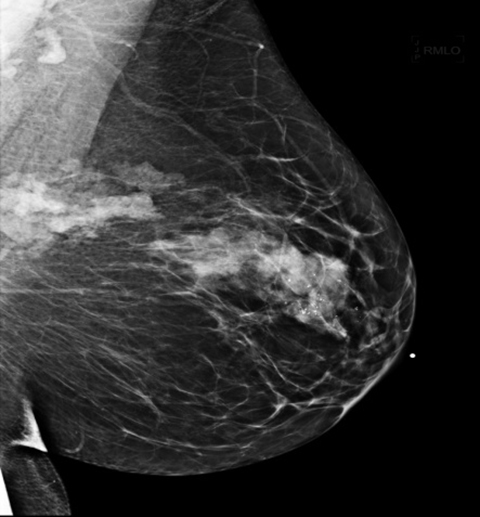

| Маммография | Рентгеновское исследование молочных желез для выявления непальпируемых образований и микрокальцинатов (отложений солей кальция), которые могут быть признаком злокачественного процесса. | «Золотой стандарт» скрининга для женщин старше 40 лет. Проводится в двух проекциях для каждой железы. |